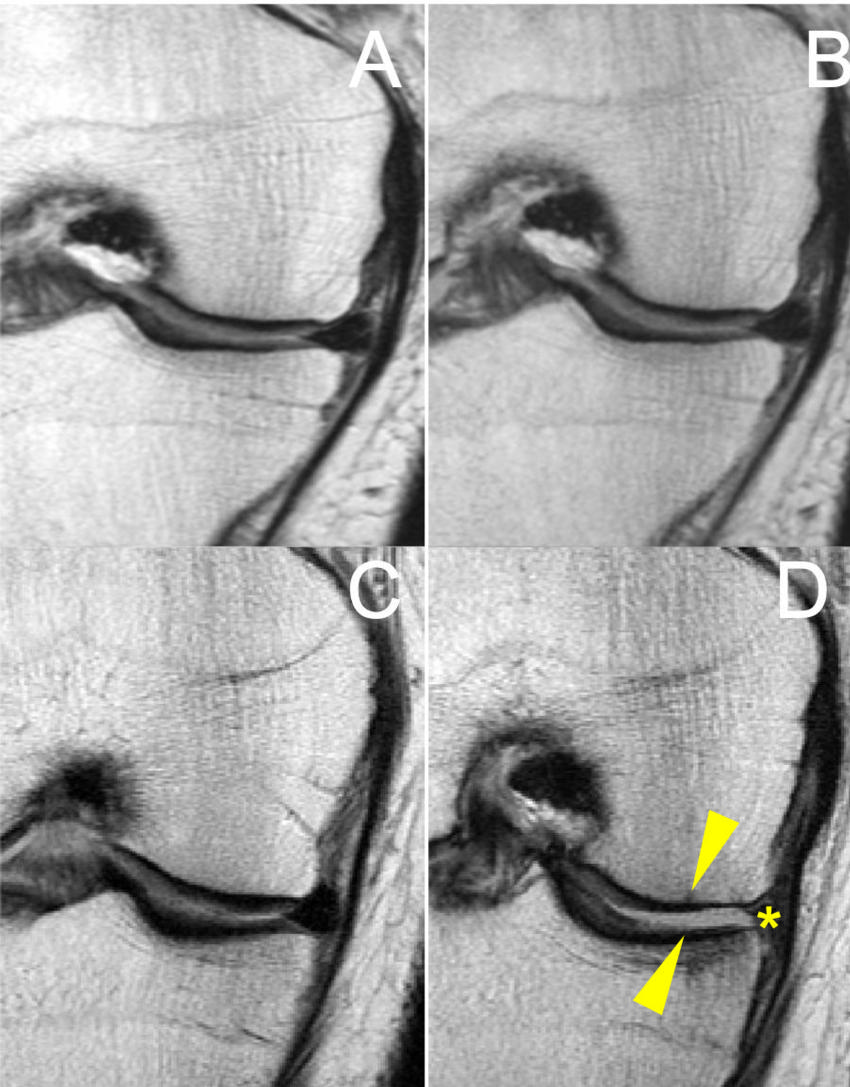

Figure 3. MR images of the right knee (A, B, C, D) at baseline (A, C) and after 48 months (B, D). Overweight 47-year-old woman in the elliptical trainer group (A-B) and overweight 64-year-old man in the racket sports group (C-D). The man in the racket sports group developed severe cartilage damage at the femur and tibia bones (arrowheads). In contrast, no cartilage damage was seen in the woman in the elliptical trainer group (A-B).